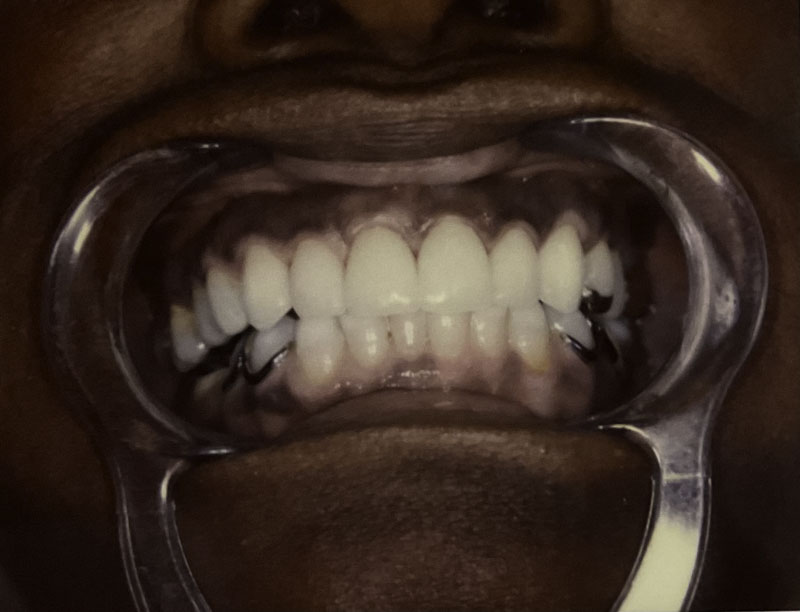

Custom Dental Veneers

Case Highlight

Before

After